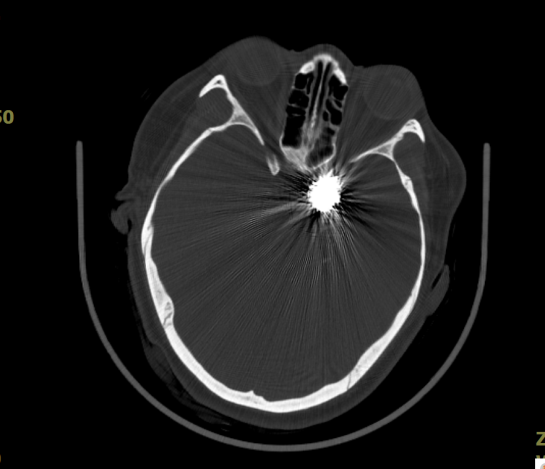

术后复查CT未见出血、梗死,术区见形态规则的弹簧圈影